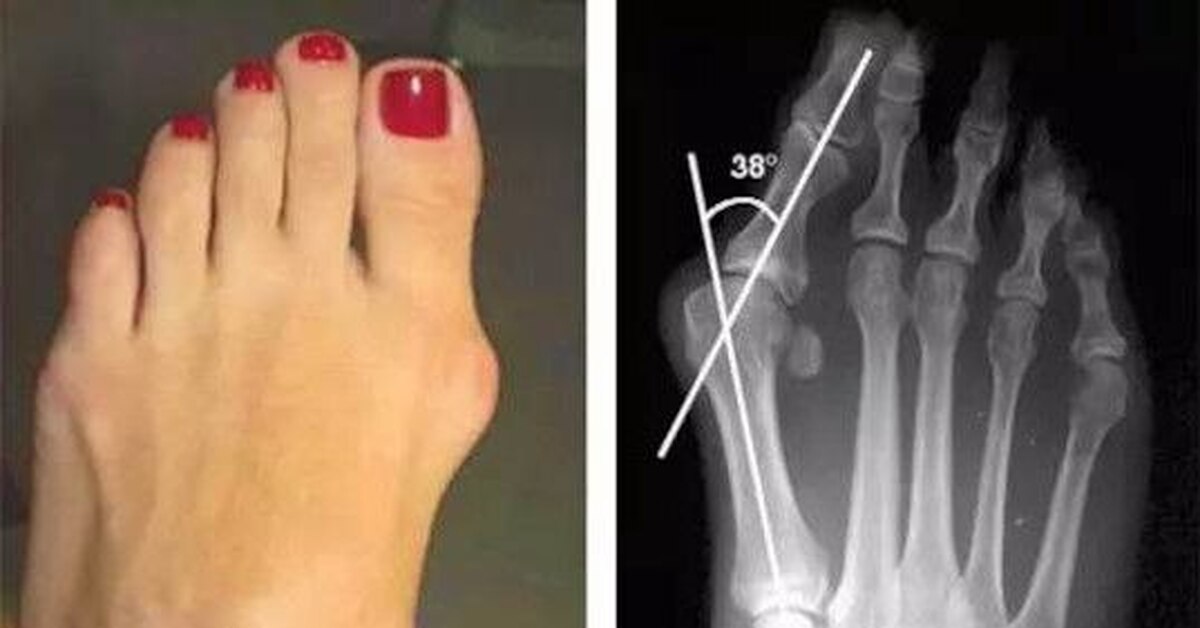

Вальгус Ног Фото